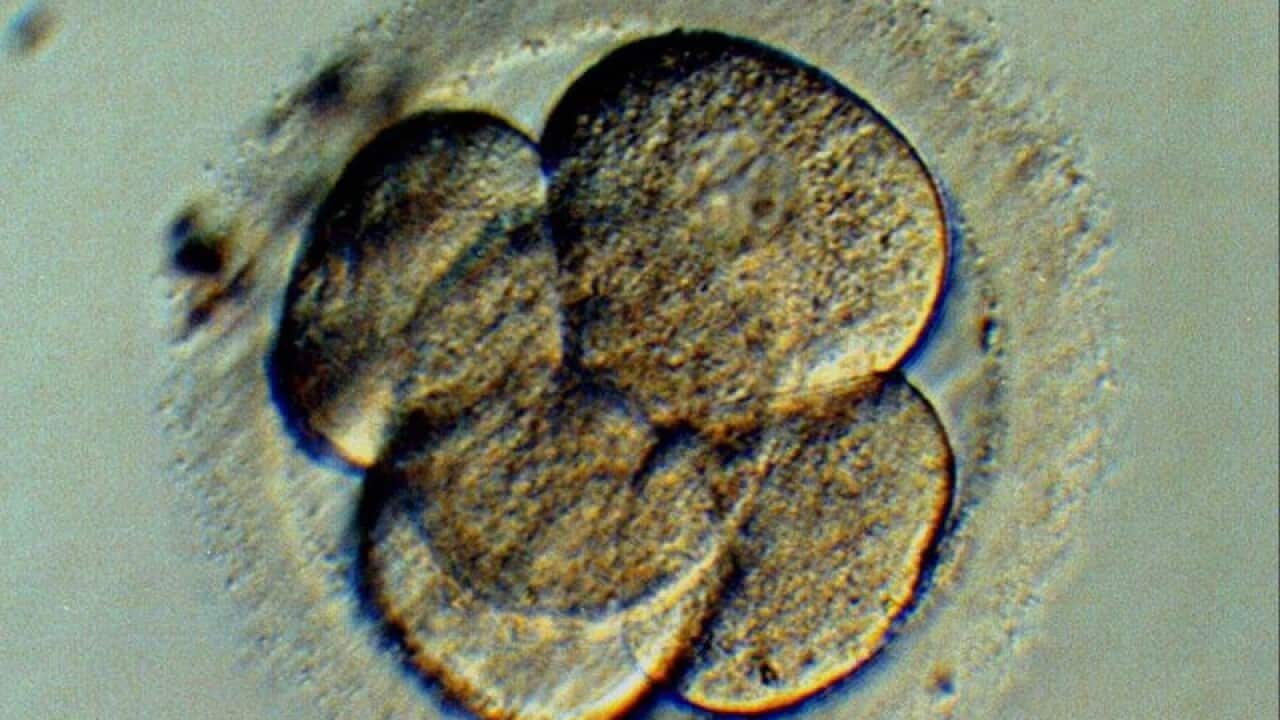

There's no difference between fresh and frozen embryos when it comes to producing IVF babies, Australian and international researchers have found.

A new study has looked at ongoing pregnancy rates and live births in almost 800 women, with one group using frozen embryos, the other fresh. It found no significant difference between the groups.

The new study showed ongoing pregnancy occurred in 36 per cent of women in the frozen group, and in 35 per cent in the fresh group. Live birth rates were also on par, at 34 per cent in the frozen group, and 32 per cent in the fresh group.